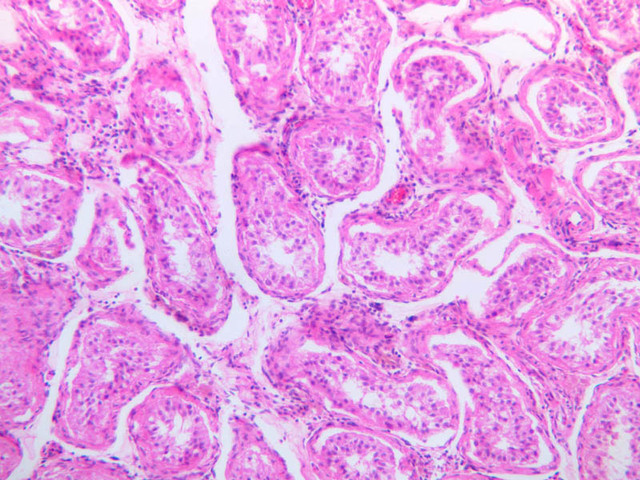

Scan a section of testis from the slide boxes at low magnification, and note the arrangement of the testicular components (slide B-80, H&E [1x-labeled, 1x, 1x]; B-81, PAS [1x, 1x]; B-82, adult monkey testis, H&E [1x, 1x, 1x, 1x, 1x] [2.5x, 10x]). A thick fibroelastic connective tissue capsule, or tunica albuginea, surrounds the testis. Within the tunica and sometimes bulging inward are a number of large blood vessels. The larger, thicker walled vascular profiles are sections through the testicular artery, which executes a highly convoluted course through the tunical plane. Closely applied to the outer surface of the tunica albuginea is the visceral layer of the tunica vaginalis, whose free surface is lined with mesothelium (B-81, PAS [2.5x-labeled]). In some specimens the parietal layer of the tunica vaginalis has been removed, but in others it is possible to find both layers of the tunica vaginalis and the potential serous space between them. How does the tunica vaginalis originate? Connective tissue septa extend inward from the tunica albuginea, subdividing the testis into a number of lobules. Within each lobule are numerous profiles of seminiferous tubules (B-82 [2.5x-labeled, 10x] [20x, 40x]). The interstitial space between the seminiferous tubules is occupied by a loose connective tissue matrix that is permeated by blood and lymphatic vessels and contains clusters of Leydig cells (interstitial cells) (B-82 [40x-labeled]).

Sperm production, or spermatogenesis, encompasses two distinct series of events: one affecting mostly the nucleus, the other affecting mostly the cytoplasm. First, there is a series of events, known collectively as spermatocytogenesis, in which rounded diploid stem cells (spermatagonia) give rise to clusters of rounded haploid cells (spermatids). Then there is a series of events, known collectively as spermiogenesis, in which the round spermatid spins a long flagellum, undergoes compaction of its nucleus, transforms its Golgi complex into an acrosomal cap, and sheds nearly all of its cytoplasm to yield a spermatazoa. Bear in mind that if you are to develop a good sense of the dynamics of sperm production, you will have to examine a number of seminiferous tubules. This is because spermatogenesis is typified by complex waves of proliferation and differentiation that sweep both around the circumference and along the length of the seminiferous tubule. Using the high dry objective, search slide B-81 for a transversely sectioned seminiferous tubule (i.e. one that presents a round profile in which a large lumen is surrounded by an epithelial wall of uniform thickness). Observe that the peripheral surface is demarcated by a continuous layer of small flattened cells containing elongated basophilic nuclei. These are contractile myoid cells (similar to the myoepithelial cells of other glands), which aid in propulsion of the luminal contents towards the excurrent duct system (B-81, testis, PAS [2.5x-labeled, 10x, 20x. 40x-labeled]; [10x, 20x, 40x]). The clearly stratified seminiferous epithelium differs in appearance from one tubular profile to another and even from one part of a single tubule to another. The seminiferous epithelium is composed of two populations of cells: proliferating cells of the germinal spermatogenic series and nonproliferating Sertoli cells. Sperm production begins with mitotic division of cells located at the tubule periphery; later events occur progressively closer to the lumen. In typical H&E preparations of seminiferous epithelium it is the distinctive qualities of nuclei that stand out against poorly defined cytoplasm (B-80, testis, H&E [20x, 40x-labeled] [10x, 20x, 40x-labeled] [10x, 20x, 40x] [2.5x, 10x, 20x, 40x]; B-82, testis, H&E [2.5x, 10x, 20x, 40x] [2.5x, 10x, 20x, 40x] [10x, 20x, 40x] [10x, 20x, 40x]). Thus, in your study of seminiferous epithelium, it is nuclear appearance that will enable you to distinguish the following cell types:

Primary spermatocytes originate from mitotic division of spermatogonia and are usually one or more cell diameters removed from the tubular periphery. Their nuclei are more or less spherical and are conspicuously larger than those of other germ cells; their chromatin is usually condensed into many thread-like structures. Most primary spermatocytes are seen in some stage of the very protracted (21-day) prophase leading up to the first meiotic (reduction) division, in which each primary spermatocyte gives rise to two secondary spermatocytes.

Spermatids

Spermatids are located next to lumen of the seminiferous tubule, where they undergo an elaborate differentiation process (spermiogenesis) that requires about 7 weeks and involves condensation of nuclear chromatin, compaction and elongation of the nucleus, shedding of nearly all cytoplasm and formation of a motile flagellum (tail). Spermatid nuclei vary in size, condensation of chromatin and shape according to the stage of spermiogenesis that they represent; however, all of them are smaller than the nuclei of any of the antecedent cell types. Spermatids at different stages of spermiogenesis may be present in a single tubule.

Sertoli cells

Interspersed among the germ cells, but generally situated near the epithelial periphery, are nuclei of the Sertoli cells. Sertoli cells span the full thickness of the seminiferous epithelium; however, because of their irregular shape and poor affinity for dyes, it is impossible to define the cytoplasmic processes of Sertoli cells in ordinary paraffin sections. Sertoli cells have large euchromatic nuclei and very prominent nucleoli. The nuclear shape is usually oval or triangular, but may also be irregular due to deep indentations of the nuclear membrane. The long axis of the nucleus is typically oriented at right angles to the basement membrane. From ultrastructural studies it is known that Sertoli cell processes make specialized contacts with germ cells as well as with processes of other Sertoli cells. Sertoli cells are the basis of the blood-testis barrier As you might expect, there are marked differences between the prepubertal and postpubertal testis. In the true prepubertal male (slide B-86, epididymis and testis, H&E [2.5x, 10x, 20x, 40x]) and in undescended testes of older males, the seminiferous tubules are solid cords of cells, consisting of spermatogonia-like cells known as gonocytes, and cells that resemble the Sertoli cells of the adult testis. Section B-78 is from the testis of an older individual and a lumen is now present (B-78, H&E [2.5x, 10x, 20x, 40x]). Even though the seminiferous epithelium of this autopsy specimen is poorly preserved, you should be able to evaluate its spermatogenic capacity. Can you identify spermatogonia and Sertoli cells? Are spermatids present? Judging from the interstitial morphology, would you expect high peripheral testosterone levels?